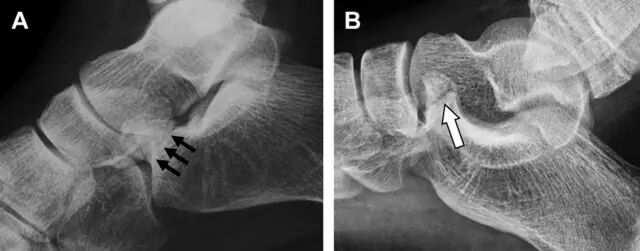

涉及到三角韧带和外侧副韧带(LCL)的复杂性骨折常常不难发现,尤其是存在表面软组织肿胀时。然而,后胫腓韧带牵拉引起的胫骨后踝骨折则很难发现。这些骨折大小不一(图 2),却很重要,因为他们常与胫骨远端螺旋骨折有关,或者是三踝骨折的一部分。

图 2 胫骨后踝骨折。A 侧位片示来源于胫骨后踝的一个小骨折碎片(箭头),因踝部扭伤导致;B 另一位跖屈损伤的患者,侧位片示一个大骨折块(箭头)